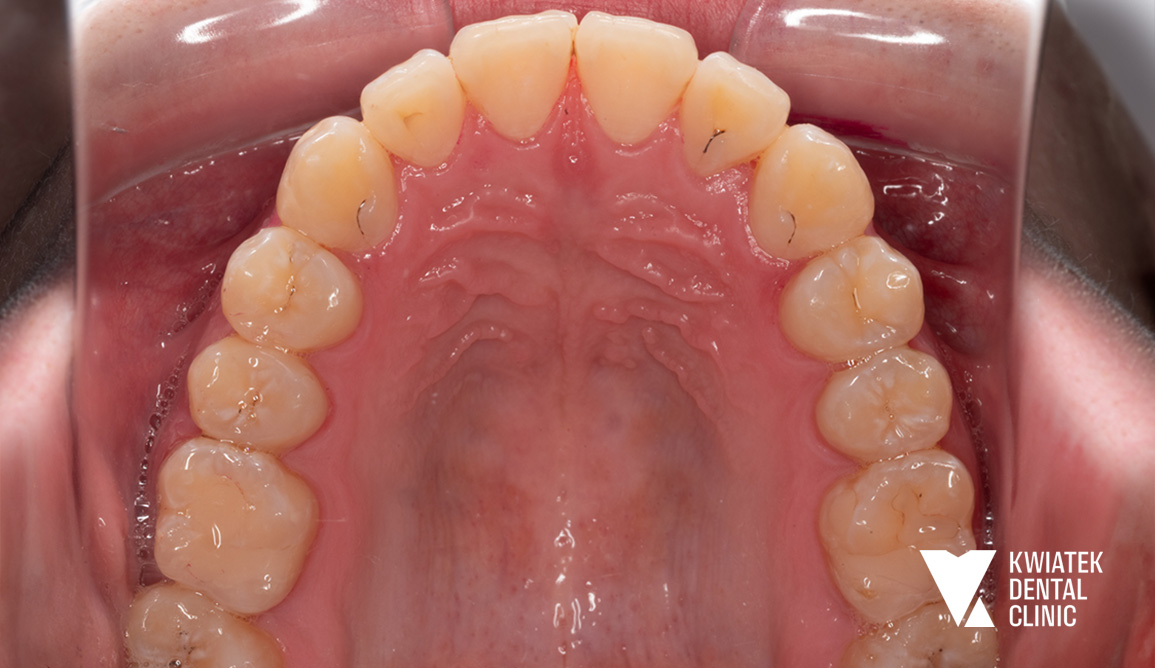

PO

Po zakończeniu leczenia zdjęto aparaty stałe z obu łuków zębowych, oczyszczono powierzchnie zębów z pozostałości kleju i wykonano dokumentację fotograficzną efektów terapii. Dla utrwalenia osiągniętych rezultatów zastosowano retencję w postaci stałego retainera oraz retainerów ruchomych dla obu łuków zębowych

Uzyskano prawidłowe ustawienie zębów w łukach, korektę zgryzu krzyżowego, właściwą relację zgryzową oraz harmonijną estetykę uśmiechu. Metamorfoza pokazuje, jak dzięki dokładnej diagnostyce, nowoczesnym technikom ortodontycznym oraz konsekwentnemu prowadzeniu leczenia można osiągnąć stabilny i naturalny efekt bez konieczności usuwania zębów przedtrzonowych.